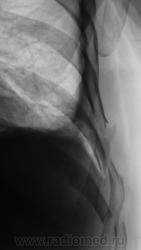

- https://radiomed.ru/sites/default/files/styles/case_slider_image/public/user/12/2.pb130018.jpg?itok=qpNgo3K0

- https://radiomed.ru/sites/default/files/styles/case_slider_image/public/user/12/3.pb130020.jpg?itok=ZQIONPdk

Я так понимаю , что справа - это случайная находка ( C-r нижнедолевого бронха , осложненный субателектазом правого легкого и правосторонним гидропневмотораксом) ?

Нет. Это ДТП.

Снимок был сделан на передвижке, качества ниже "хренового", но уже тогда газ в плевральной полости справа был, была с обеих сторон огроменная подкожная и межмышечная эмфизема.